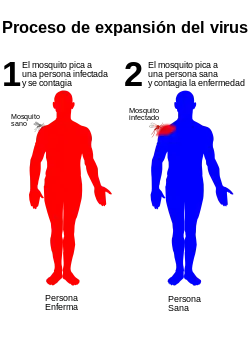

Transmisión

El vector principal del dengue es el mosquito Aedes aegypti. El virus se transmite a los seres humanos por la picadura de mosquitos hembra infectadas. Tras un periodo de incubación del virus que dura entre 4 y 10 días, un mosquito infectado puede transmitir el agente patógeno durante toda su vida.[4] También es un vector el Aedes albopictus, este es un vector secundario cuyo hábitat es Asia, aunque debido al comercio de neumáticos se ha extendido en los últimos años a América y Europa. Tiene una gran capacidad de adaptación, y gracias a ello puede sobrevivir en las temperaturas más frías de Europa, lo cual es un grave problema de salud pública. Su tolerancia a las temperaturas bajo cero, su capacidad de hibernación y su habilidad para guarecerse en microhábitats son factores que propician su propagación y la extensión geográfica del dengue.[32]

Las personas infectadas son los portadores y multiplicadores principales del virus, y los mosquitos se infectan al picarlas. Tras la aparición de los primeros síntomas, las personas infectadas con el virus pueden transmitir la infección (durante 4 o 5 días; 12 días como máximo) a los mosquitos Aedes.[4]

El dengue se transmite a los humanos por el mosquito Aedes aegypti, el cual es el principal vector de la enfermedad en el hemisferio occidental, aunque también es transmitido por el Aedes albopictus.

No es posible el contagio directo de una persona a otra.[16][17]